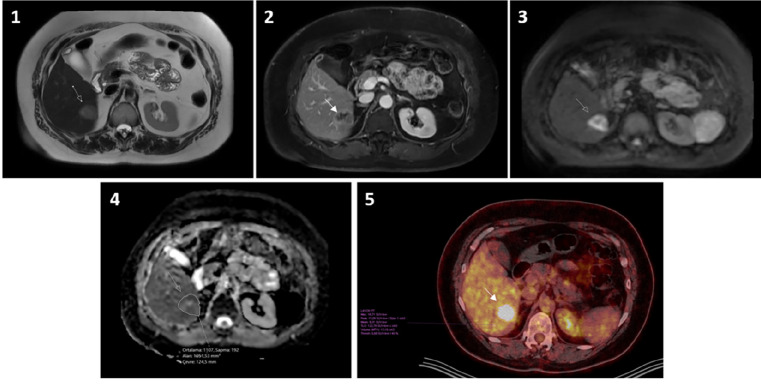

Methods: Abdominal magnetic resonance (MR) scans performed between April 2021 and 2024 using the 3T MR scanner were retrospectively evaluated. Thirty-three patients with liver metastases, less than one month between magnetic resonance imaging (MRI) and PET/CT, no treatment during this period, and lesions larger than 1 cm were included in the study. In each MRI scan, an index lesion was selected for ADC measurement. The radiologist and nuclear medicine specialist measured the same index lesion without the patient being informed of the results.

Results: The mean age of the 33 patients was 59±12 years, with 17 (51%) men and 16 (49%) women. The mean size of the index lesions was 27±9 mm. In MRI, mean ADCmin: (0.54±0.2) ×10-3mm2/s; ADCmean: (1.02±0.2) ×10-3mm2/s; ADCmax: (1.48±0.44) ×10-3mm2/s; and region of interest area was calculated as 6±4.6 cm2. In PET/CT, mean SUVmean: 5.8±3.3; SUVpeak: 6.8±4.3; SUVmax: 10.7±5.6; and metabolic tumor volume: 12.1 (7.4-20.7) cm3. No statistically significant correlation was found between ADC and SUV values.

Conclusion: There was no correlation between ADC and SUV values in liver metastases. Prospective studies with a large patient group are needed.